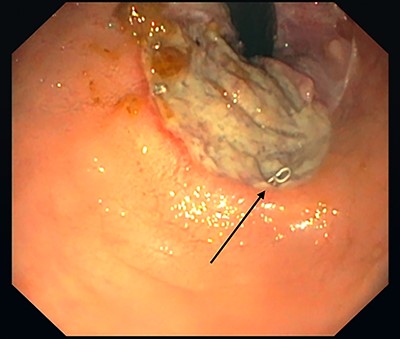

Five months after the initial operation a flexible sigmoidoscopy revealed a large ulceration 3.5 cm from the anal verge (Fig. 1). The consecutively performed magnetic resonance imaging (MRI) suggested a subcutaneous fistula at 6 o’clock.

Rectal ulcer, 3.5 cm from the rear circumference. Stapler after hemorrhoidopexy (black arrow).